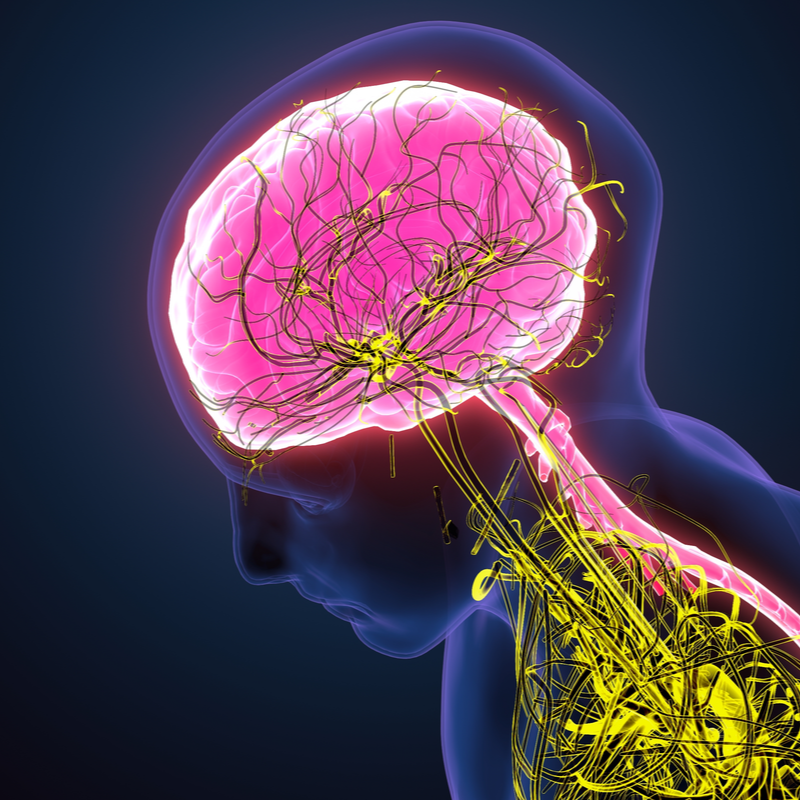

Brain tumour

Brain tumour bening

Meningioma

Oligoastrocytoma

Oligodendroglioma